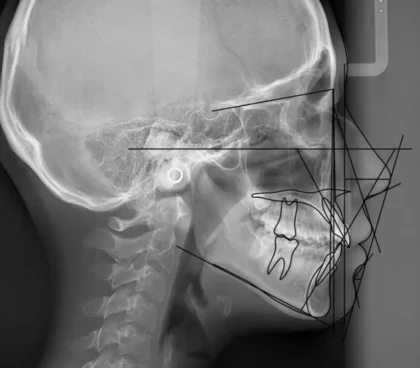

リケッツはEラインに対し上唇が4mm、下唇が2mm内側にあるのが理想としていますが日本人はやや鼻が低いため上唇が2mm内側、下唇がEライン上にあるのが理想的とされています。当院では鼻の高さから理想的なEラインになるようにレントゲン撮影を行い矯正治療にて歯の角度を変え理想的な位置に移動させて理想的なバランスを目指します。

当院では、矯正治療の成功に欠かせない正確な診断のため、セファロ(頭部X線規格写真)をはじめとしたデジタル機器を積極的に導入しています。さらに、AI技術を用いた詳細な骨格・歯並びの解析や、治療結果のシミュレーションを行うことで、患者様ごとに最適な治療計画を立案しています。

これらの先進的な診断システムにより、単に歯並びを整えるだけでなく、口元や顔全体のバランス、特に横顔の美しさを最大限に考慮した治療が可能です。治療の過程でもAI解析を活用し、効果をリアルタイムで評価。必要に応じて細かな調整を加えることで、より正確で効果的な矯正治療を実現しています。

- Eライン(Esthetic Line)

1-1 上顎、下顎の前後的位置関係

1-2 歯の傾き(角度)

1-3 鼻の高さ - 鼻唇角(Nasolabial Angle)

鼻唇角(Nasolabial Angle)は鼻下線(鼻の先端と鼻の付け根を結んだ線)と上唇線(鼻の付け根と上唇を結んだ線)の交わる角度のことです。当院での治療目標として男性では約90°前後、女性では100°前後を目標にしています。 - オトガイ唇溝(labiomental sulcus)

オトガイ唇溝(labiomental sulcus)オトガイの上部、下唇の間にできる溝です。 - 上唇の傾斜角(Cant of upper lip)

上唇の傾斜角(Cant of upper lip)はN点(ナジオン)という眉間にある骨からFH平面(フランクフルト平面)に対しての垂線(ナジオンライン)と上唇線(鼻の付け根と上唇を結んだ線)の交わる角度です。FH平面とは眼窩下点(眼窩下縁)と外耳道上縁を結んだ線に事です。この角度の日本人男性の平均値は17.1°±10.4°、日本人女性の平均値は17.9°±5.4°とされています。当院では上唇の傾斜度は鼻唇角の補足として使用しています。なぜかというと鼻唇角は鼻の形に大きく左右される為です。鼻が上向きの人の場合、鼻唇角は大きな角度になります。そのような時に上唇の位置を決める際にこの上唇の傾斜度をみることでバランスが分かります。 - Z-angle

下唇の最突出点とオトガイ部最突出点を結ぶ線とフランクフルト平面のなす角度で評価します。